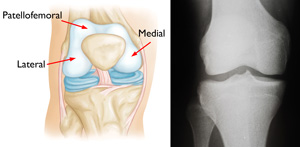

Your knee is divided into three major compartments:

(Left) A normal knee joint: The medial, lateral, and patellofemoral compartments are shown with red arrows. (Right) An x-ray of a normal knee joint showing healthy space between the bones.